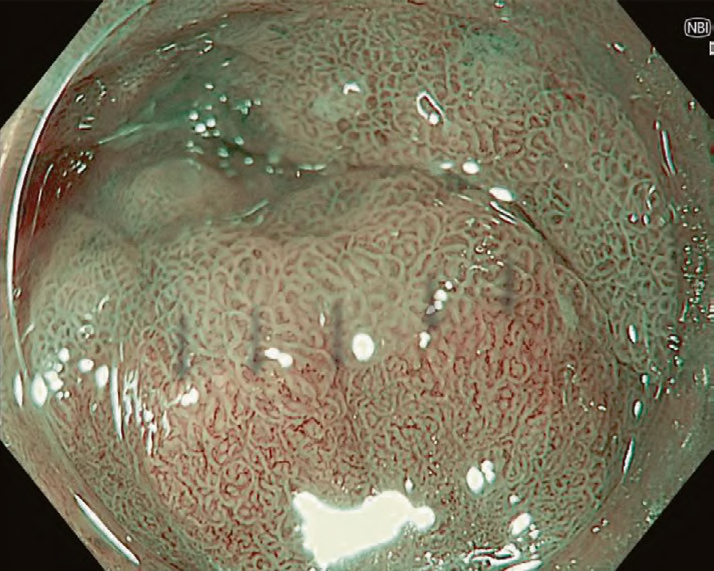

Mucosal and vascular patterns in each NBI image were classified as “regular” or “irregular” based on characteristics agreed upon by the working group (Table 1). Regular mucosal patterns were marked by circular, ridged/villous, or tubular patterns, and irregular mucosa was marked by absent or irregular surface patterns (Fig. 1a, b). Regular vascular patterns were defined by blood vessels situated regularly along or between mucosal ridges and/or those showing normal, long branching patterns; irregular vascular patterns were marked by focally or diffusely distributed vessels not following the normal architecture of the mucosa (Fig. 1c, d). Images not readily identified as regular or irregular were deemed uncertain.